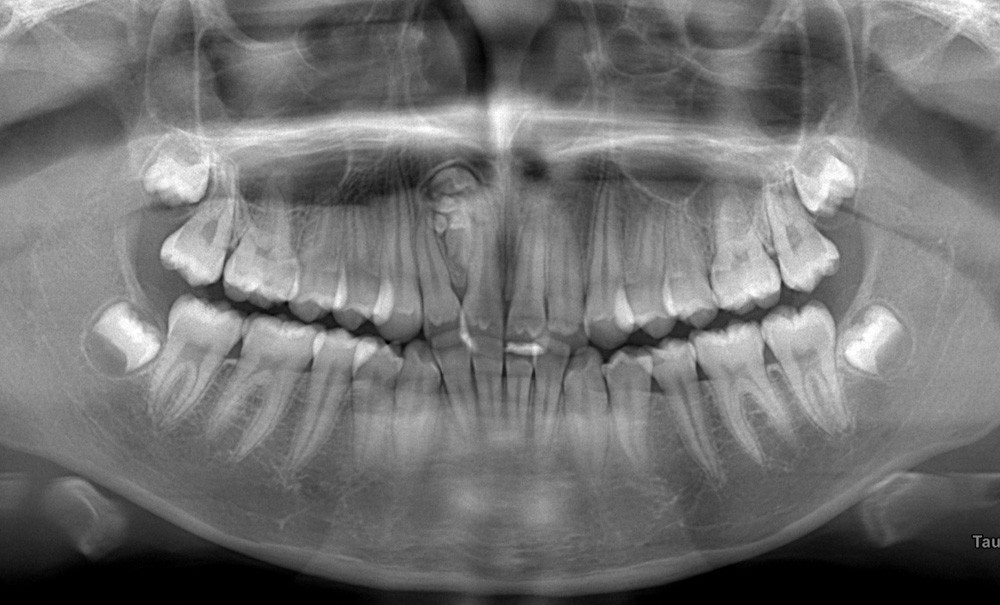

Que voyez-vous sur les coupes du CBCT présentées aux figures 2 à 6 ?

Les images CBCT mettent en évidence une lésion radio-opaque bien circonscrite au niveau antérieur maxillaire, constituée de multiples petites structures calcifiées à morphologie « dentaire ». L’aspect en amas de « micro-dents »…